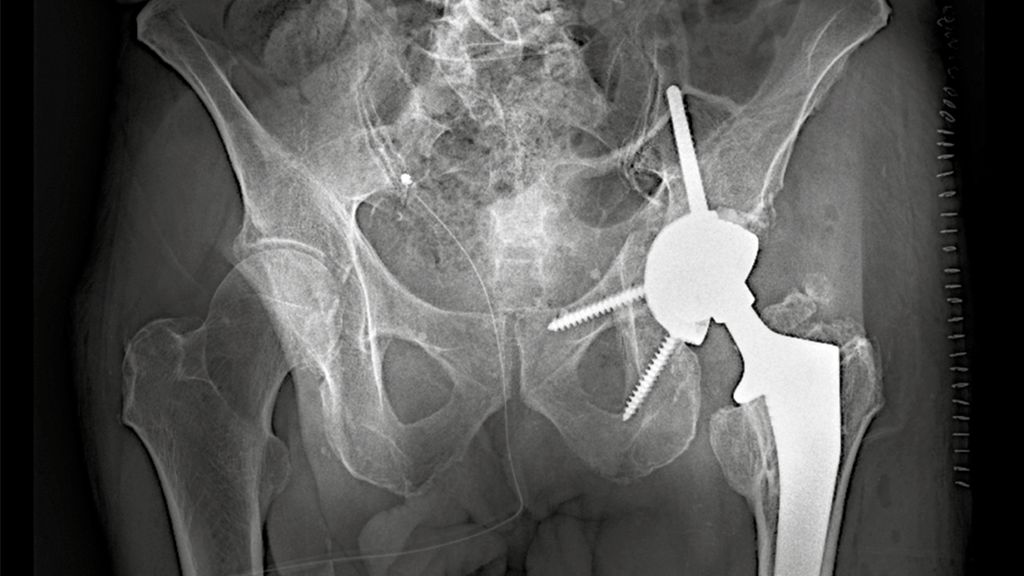

Abb. 1: Zementfreie, sphärische, am Pol abgeflachte Rekonstruktionsschale mit neun Bohrungen für Spongiosaschrauben (Ø 6,5mm) und drei kranialen Bohrungen für Spongiosaschrauben (Ø 8mm)

Hochbetagte Patientinnen und Patienten können in der Regel nicht mobilisiert werden, ohne die betroffene Extremität voll zu belasten. Die Ursachen hierfür können dabei sowohl körperlicher als auch kognitiver Natur sein. In diesen Fällen gewinnt die primäre endoprothetische Versorgung mit Rekonstruktionspfanne an Bedeutung (Replace-in-situ-Prinzip). Diese gewährleistet in Kombination mit der zentralen Ileumschraube eine sofortige stabile Primärverankerung der Hüftpfanne auch bei komplexen Frakturmustern und ermöglicht somit eine frühe Vollbelastung sowie Remobilisation. Ein Beispiel einer solchen Rekonstruktionspfanne stellt die Mutars® PRS (Pelvic Revision Shell) dar. Die zementfrei implantierte Rekonstruktionsschale von Implantcast zeigt Abbildung 1.

Implantation der PRS-Rekonstruktionspfanne

Die PRS-Pfanne zeichnet sich durch ihre massive Bauweise, multiple Schraubenoptionen und die Möglichkeit einer zentralen Ileumschraube aus. Nach Einbringen der Pfanne wird diese korrekt ausgerichtet (Inklination ca. 40–45°, Anteversion ca. 15–20°). Der entscheidende Schritt ist die Platzierung der zentralen Ileumschraube. Dafür wird unter Bildwandlerkontrolle ein Bohrdraht in den supraazetabulären Korridor gesetzt (Abb. 3a u. 3b) und mit dem 6-mm-Bohrer überbohrt. Anschließend wird die Schraube durch das entsprechende Positionsloch der Pfanne in den supraazetabulären Anteil des Iliums eingebracht. Dabei ist auf eine ausreichende Schraubenlänge zu achten, um eine stabile Verankerung zu erzielen. Die zentrale Schraube übernimmt eine lasttragende Funktion und wirkt wie eine intrapelvine Abstützung. Zusätzlich wird die Pfanne mit Schrauben im Sitzbein und/oder dem Schambeinast fixiert (Abb. 4). Die PRS-Pfanne erlaubt hierbei eine flexible Schraubenplatzierung, was insbesondere bei komplexen Frakturmorphologien von Vorteil ist.